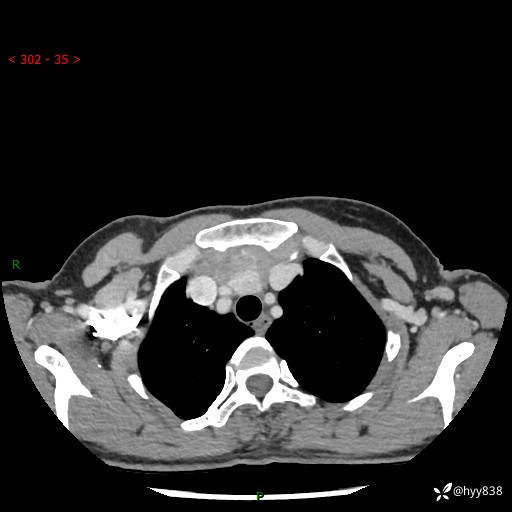

胸部CT平扫